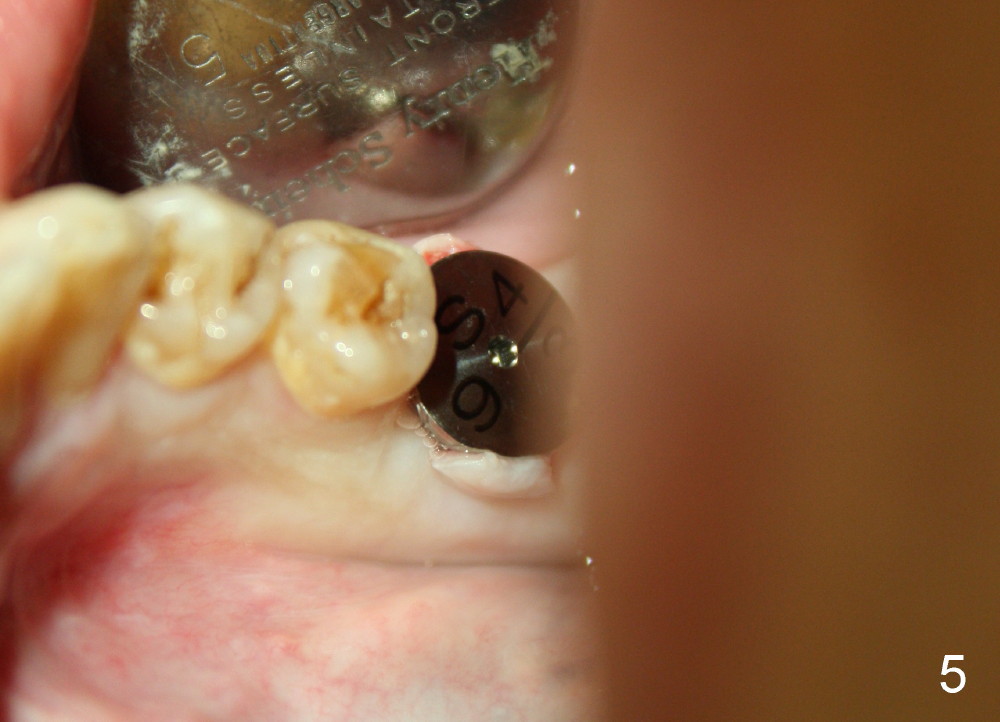

Fig.1 and 2 show a 5.3x12 mm bone level implant immediately and 6.5 months post placement, respectively. The gingiva looks normal at the site of #30 6.5 months postop (Fig.3). A small incision is made for uncover and a large healing abutment (9.2 mm) is placed (Fig.4 (buccal view), 5 (lingual)). It appears that an interdental papilla forms instantaneously (Fig.4 *). The wound is covered by periodontal dressing. To reduce the chance of post-implant infection, several things should be done. First. the extraction socket should be thoroughly debrided, copiously irrigated and soaked with an antibiotic. Second, any gaps remaining after implant placement should be filled with bone graft, which could be mixed with an antibiotic. Third, the wound should be closed as tight as possible. Either the implant is buried (bone level) or a short abutment over a tissue-level implant or healing abutment over a bone level implant is placed so that periodontal dressing can be applied around the wound. Fourth, an antibiotic is taken pre- and post-op. There is no bone loss around the implant 21 months post cementation (Fig.6) or 4 years 9 months post cementation (Fig.7). Return to Professionals Implant Failure Xin Wei, DDS, PhD, MS 1st edition 07/26/2014, last revision 06/13/2019